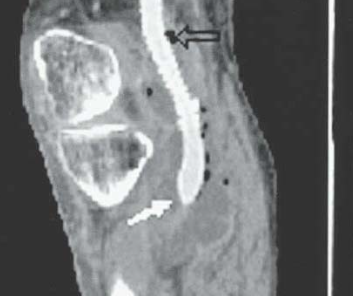

- Collection

- Bulles d’air

- (Post-op immédiat on peut avoir 1-2 bulles d’air)